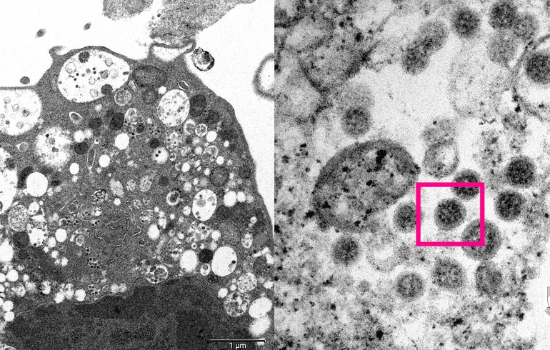

São Paulo confirma 4° caso da ômicron; paciente não tem histórico de viagem (Foto: Universidade de Hong Kong)